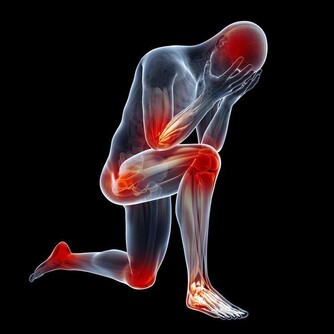

1.未老先衰、心髒病纏身血液的循環由橫向變成豎向,這就造成大腦供血不足和心血管系統超負荷運行。

輕者產生了禿頂、眼花、白髮、精神不振、易疲勞、未老先衰;重者腦疾病和心髒病纏身。

2.心臟器官下垂、肥胖造成許多腸胃和心臟器官下垂病,使腹部和大腿部脂肪淤積,產生腰圍線和大腹肥胖。

3.頸椎、腰椎等疾病加重在引力作用下,致使頸部、肩背部及腰部等部位的肌肉承受更多的負荷,造成過度緊張,產生肌肉勞損、頸椎、腰椎、肩周炎等疾病的加重。